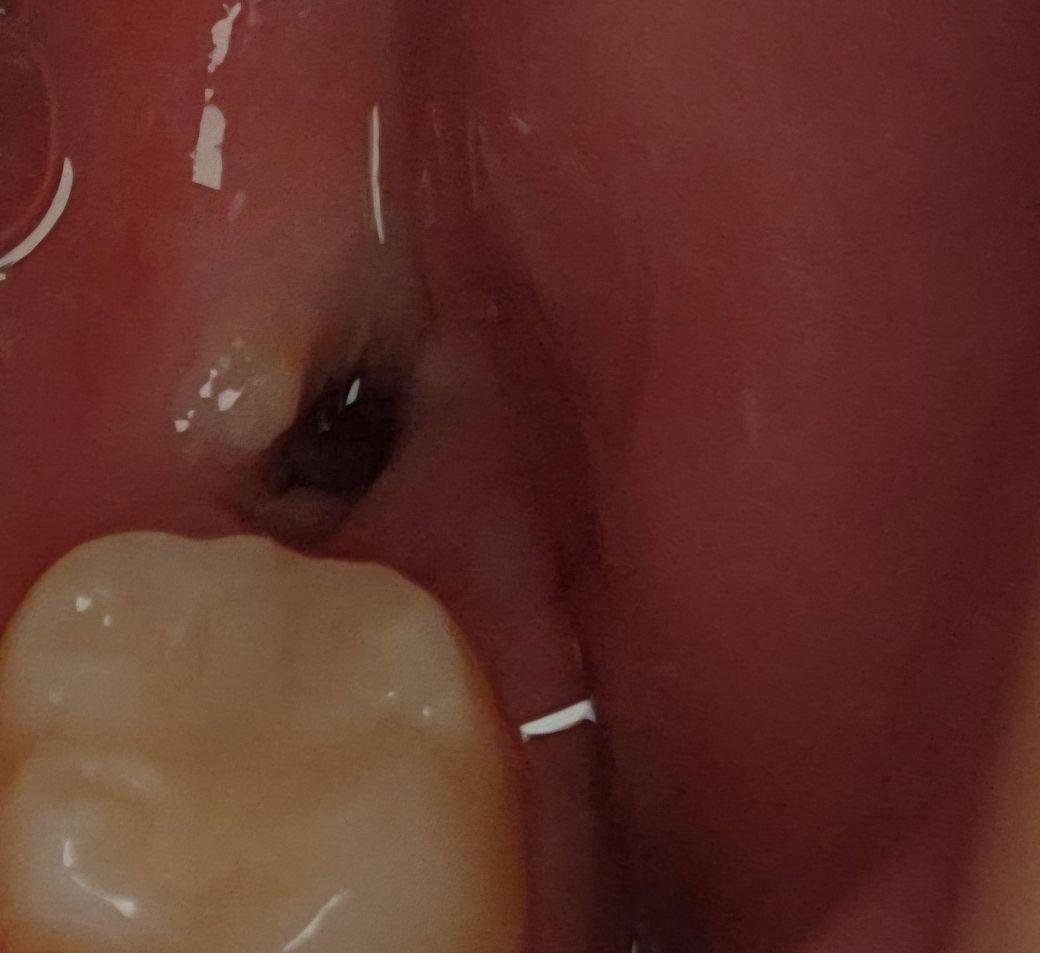

사랑니 발치 5일차 드라이소켓 아닐까요?

저번주 금요일에 빼서 오늘 5일차인데 벌써 혈병이 안보여요 저번에 반대쪽 뺐을 땐 더 오래걸렸는데 이번엔 어제부터 혈병이 거의 안보일 정도로 빠르더라고요 통증은 살짝 욱신거리는 정도만 있고 심한 악취가 난다거나 그런건 아닌데 드라이소켓 가능성은 없을까요? 인터넷에 검색해보니까 저랑 비슷한 사진 보여서 걱정이네요

사진상으로 보면 잘 아물고 있습니다. 아직 잇몸이 다 아문상태가 아니니 음식물이 남아 있지 않도록 관리를 잘해주세요.

발치를 한 부분 내부에는 혈병이 있는 것으로 보입니다. 드라이소켓이 생겼을 경우 강한 통증이 유발되기 때문에 강한 통증이 없다면 드라이소킷이 아닐 가능성이 높습니다.

자세한 확인을 위해서 치과에서 진료를 받아보는 것을 권유드립니다.

사진상으로는 아무문제가 없어보이며 드라이소켓 가능성은 없어보이니 걱정안하셔도 됩니다.

사진상 드라이소켓의 양상 보이지 않습니다 혈병은 원래 발치 후 2일차이후에는 흡수되어 안보이는게 맞습니다